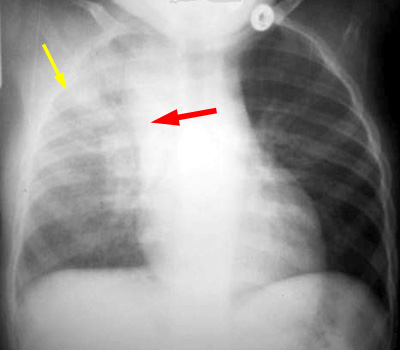

Primary TB produces a focal lobar consolidation in any pulmonary lobe. Hilar adenopathy and pleural effusions are common and should alert the radiologist to the possibility of TB.